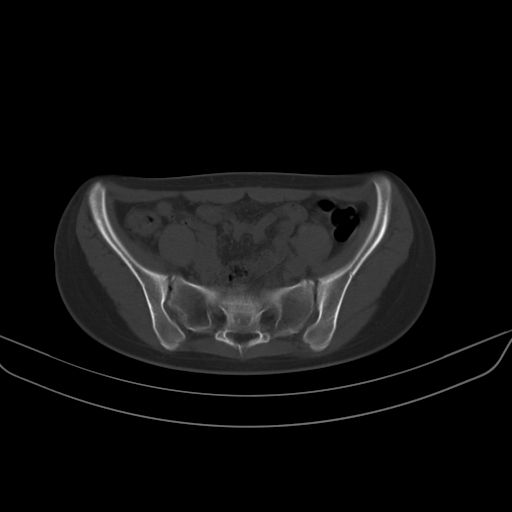

以下是引用zsl6918在2008-7-11 21:40:00的发言:[br]双侧骶髂关节骨质破坏以下三分之一为主,符合强直性脊柱炎表现

以下是引用zhangzhongshou在2008-7-11 21:41:00的发言:[br]患者是女性,hla-b27抗原(—),首先不太考虑强直性脊柱炎,建议查类风湿因子,骶髂关节改变考虑类风湿性关节炎可能性大,建议进一步检查。